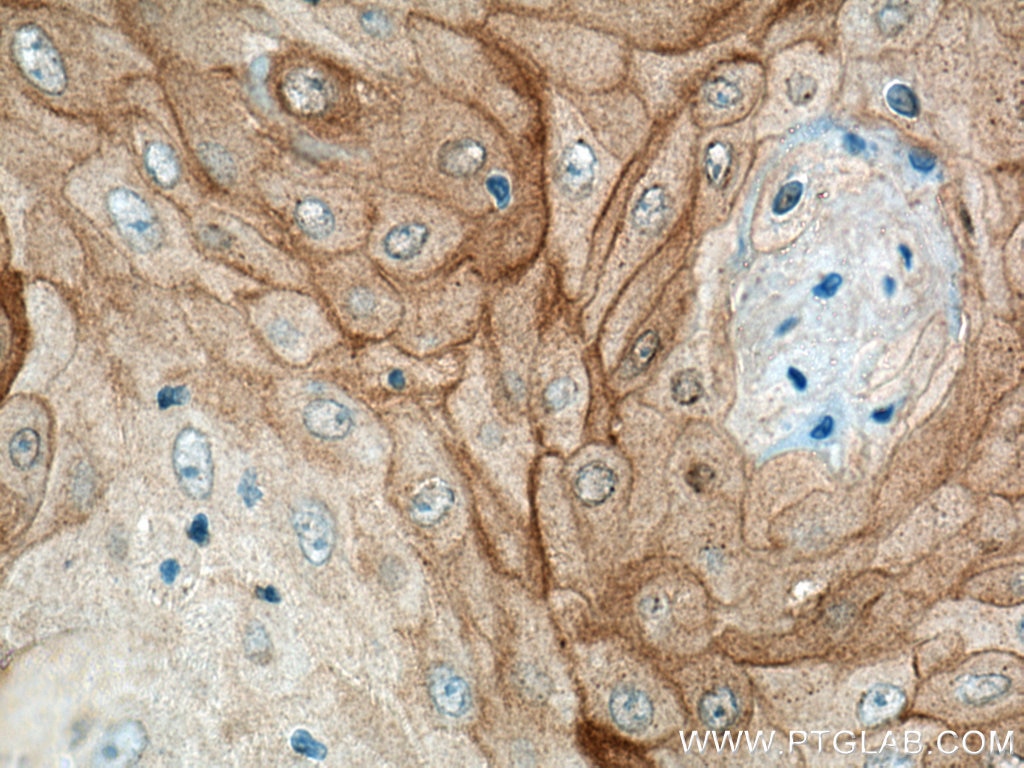

| Positive IHC detected in | human skin cancer tissue, human colon cancer tissue Note: suggested antigen retrieval with TE buffer pH 9.0; (*) Alternatively, antigen retrieval may be performed with citrate buffer pH 6.0 |

| Immunohistochemistry (IHC) | IHC : 1:200-1:800 |